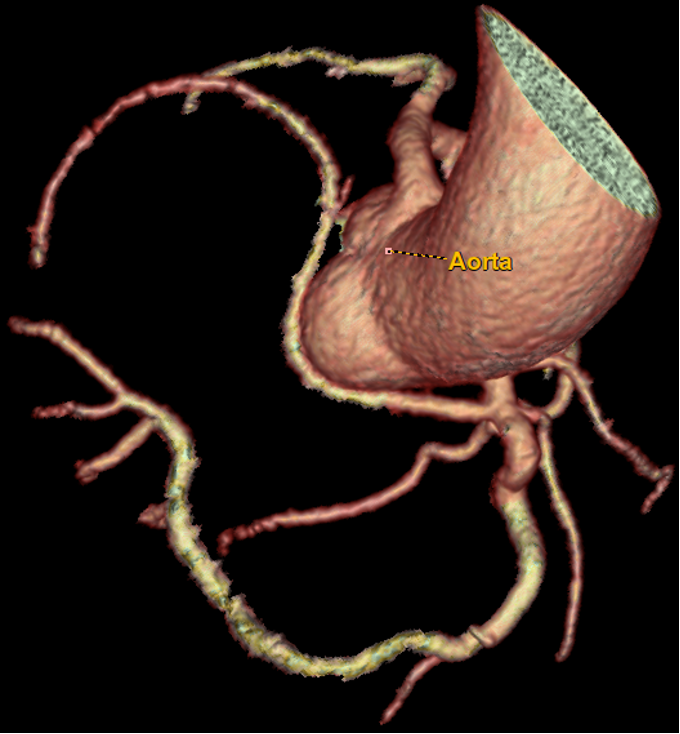

Background: Anomalous aortic origin of coronary arteries (AAOC) is a congenital condition that may affect the main three epicardial coronary vessels. The estimated prevalence of CCAs is variable, ranging from 0.21 to 5.79% based on angiography, CT, autopsy. Aim and methods: We retrospectively investigated all the angiographies and CTs performed over a 12 month-period between 2023 and 2024 at our peripheral referral center, which serves suburban areas of five cities. The aim was to assess the clinical incidence and implications of AAOC while evaluating the indications for these imaging examinations. Results: Among a total of 1100 coronary angiograms and 150 CTs, AAOC was found in 8 cases, with 4 by the former (0.37%) and 4 (2.7%) by the latter. In the cath lab, AAOC was often an incidental finding in patients with cardiovascular risk and suspected ischemic coronary artery disease. Three patients presented anomalous origin of the left circumflex artery (LCX) from the right sinus of Valsalva (Figures 1 and 2) and one patient had a left anterior descending artery (LAD) originating from the LCX. In patients diagnosed via CT, the cohort was younger, with presentations including electrocardiographic or echocardiographic abnormalities. One patient showed coronary arteries originated from the sinotubular junction (STJ). Another patient had a retroaortic LCX originating from the right sinus of Valsalva alongside an intramyocardial LAD. Two patients presented with a right coronary artery (RCA) originating from the left sinus of Valsalva (Figure 3). All patients were discharged without further interventions and were placed on routine follow-up schedules. Conclusions: AAOC remains a poorly understood condition with potential clinical implications. This small investigation provides a picture of the clinical incidence of AAOC in our geographical area, aiming at increasing the awareness of the disease in daily clinical practice. Improved stratification of patients with AAOC is essential to optimize management and may be provided by larger outcome trials.